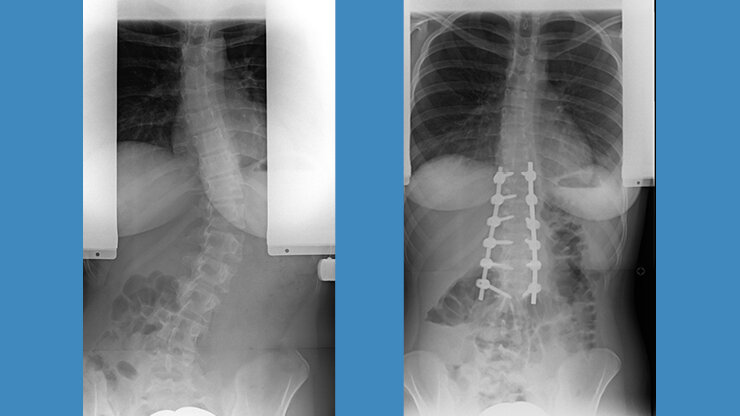

Ventrale Skoliose-Operation

Bei der Operation von ventral, also von vorne, wird entweder durch den Brustkorb oder den Bauch mit seitlichen Zugängen der vordere Anteil der Wirbelsäule erreicht. Diese Methode war bis vor einigen Jahren sehr populär, weil besonders kurzstreckig operiert werden konnte. Sie eignet sich jedoch nur für einbogige Krümmungen der Brust- oder Lendenwirbelsäule und hat den Nachteil, dass der Brustkorb geöffnet werden muss, wovon man sich einige Zeit erholen muss.

16 jähriger Junge mit primär thorakaler Krümmung

45 jährige Frau mit alter idiopathischer Skoliose